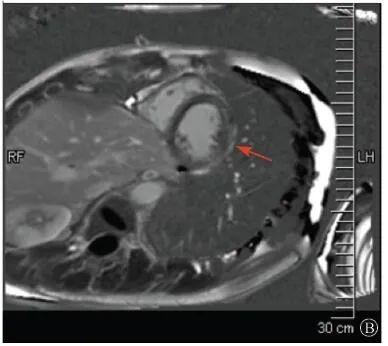

左室壁较广泛心外膜下延迟强化,可见左室下后壁肌小梁增多(箭头所示)

图1 患者外院磁共振心肌灌注延迟动态成像